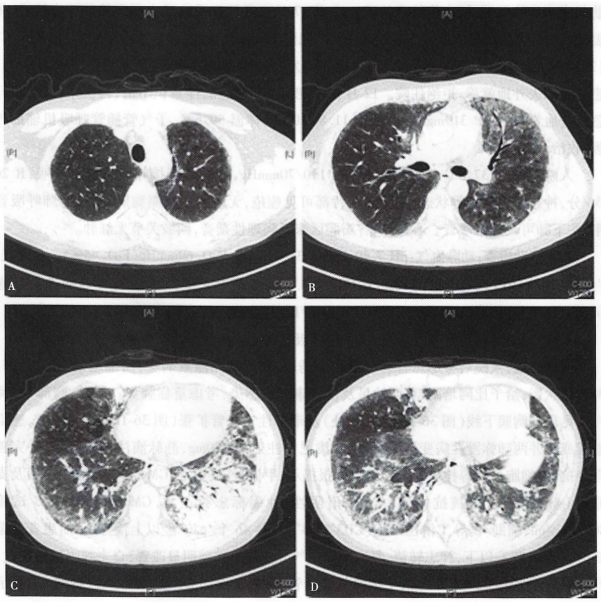

考虑治疗有效,1月21日再次给予环磷酰胺0.8 g静脉滴注治疗。1月22日再次复查胸部CT提示病灶较1月17日进一步好转(图4),将激素调整为泼尼松60 mg/d分次口服,并带药出院,建议2月21日再次来院行环磷酰胺治疗。患者2月8日在我科门诊复诊,再次复查胸部CT示两肺病灶较1月22日好转明显(图5)

图4  复查胸部CT提示病灶较前进一步好转

图5  复查胸部CT提示病灶较前好转明显